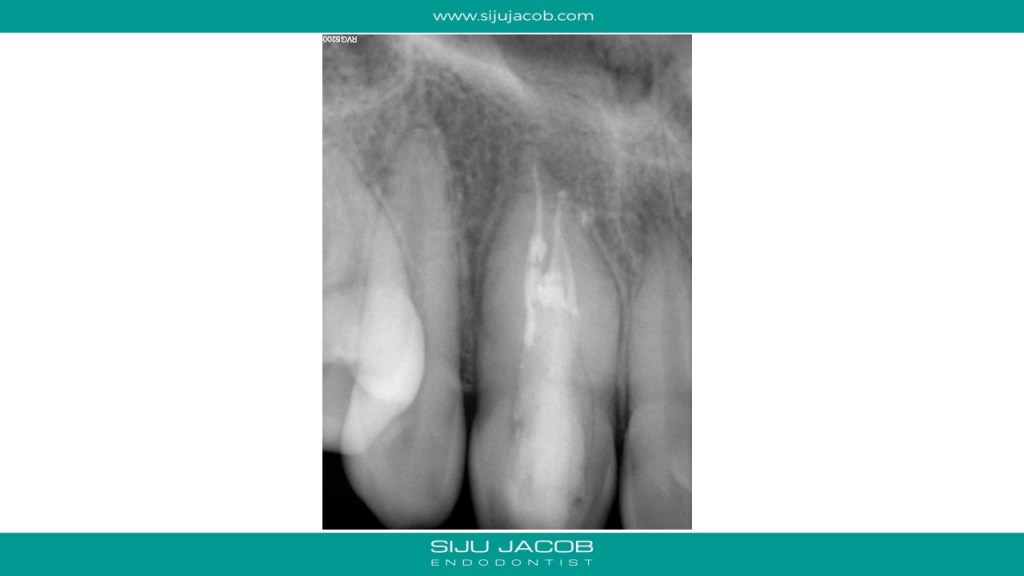

I initially thought of treating only the necrotic dens in this case because the tooth responded to heat and cold indicating that the apical lesion was probably from the dens. But, after the initial visits, the patient had persistent pain. So, I opened up both the canals, one of which was very hyperemic. I put this tooth on calcium hydroxide for 12 months and Obturated after the lesion healed. Placed Fiber-posts to strengthen the tooth. No crown for now.